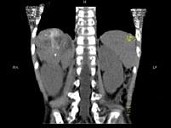

男孩,5岁。消瘦、贫血、纳差和腹部包块3个月余, CT如图所示,下列说法正确的是

A、右侧腹腔内可见一巨大软组织肿块影,其边界欠清楚

B、肿块密度不均匀,可见片状的较高密度,考虑为出血,也可见点状的钙化影

C、该病灶来源于肝脏,考虑为肝母细胞瘤

D、该病灶来源于右肾上腺,考虑为神经母细胞瘤

E、该病灶来源于右肾,考虑为肾胚胎瘤